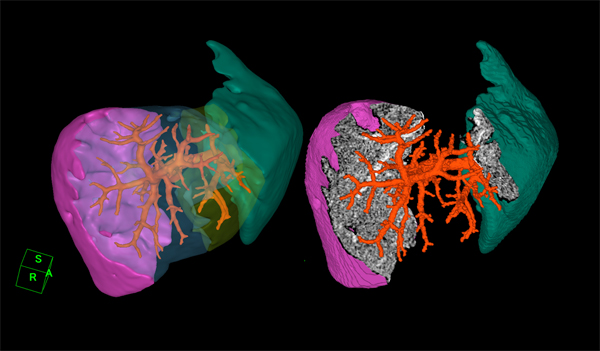

■ブラッシュアップ,そして更なる機能強化が図られた「新・肝臓解析ソフトウェア」

肝臓解析を行う目的は,肝移植や肝切除の際に切除部分の体積が肝臓全体に対してどれくらいか,残肝はどれくらいの容積であるかを術前に調べることにあります。切除体積を計算することによって手術が肝臓に及ぼすダメージを推測でき,予後の判定に役立てることができます。また体積計算だけでなくポリゴン表示やカット断面にグレイスケールの信号値を当てはめて表示するなどの工夫を施すことで臨床医にとって術中に注目される脈管の箇所をよりイメージしやすいように開発されています。

今回注目して頂きたい機能の一つ目は,RIなどの機能検査との融合です。この機能強化により,以前より豊富なデータに基づく核医学の情報を,より治療用に情報を抽出することが可能になると考えています。しかし,前述の通り3次元画像として収集されるCTやMRIのデータに対してSPECTなどのRIを用いた機能画像は,一般的に形状情報に乏しく,また違うモダリティ,違う検査日で撮影されることが多いです。そのため3次元データの肝臓部分に対して機能画像中の同一部位を重ねあわせることは,ほぼユーザの目視によって行うしかありませんでした。

新・肝臓解析では,独自のアイディアに基づいた新しい非剛体レジストレーション手法を搭載し,形態画像と機能画像の有機的な融合を実現しました。この手法は,複数フェイズを使用するケースや,MRIなどにも応用可能となっており,これがもう一つの注目して頂きたい機能です。